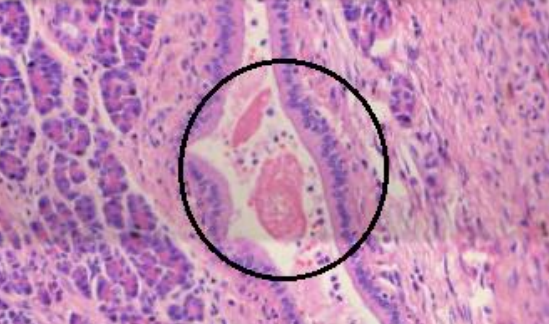

2. Pancreatite crônica calcificante (A484)

1. Fibrose, muita fibrose

1. Septos muito espaçados

2. Ductos dilatados com rolhas proteicas

1. Ácinos atrofiados

1. Ácinos próximos das áreas fibrosadas são menores